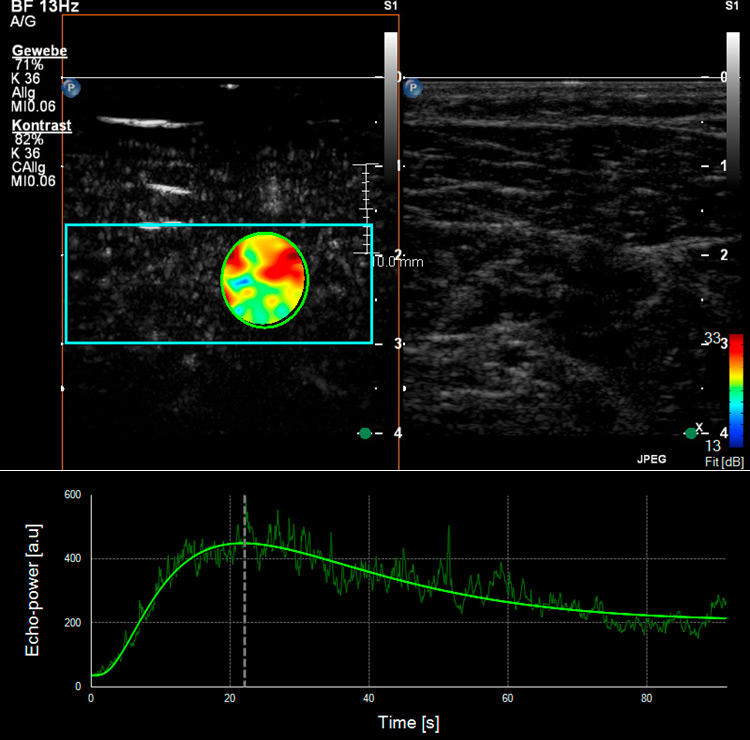

Figure 4

Skeletal muscle microperfusion on CEUS in a healthy volunteer (A) and a patient with peripheral artery disease (B). Corresponding time-intensity-curves of a region of interest (green circle) within the skeletal muscle (soleus muscle) after bolus injection of the ultrasound contrast agent with different shape in the healthy volunteer compared to the patient with peripheral artery disease.

Different studies have already used CEUS to analyse skeletal muscle perfusion in patients with PAD and with different cardiovascular risk factors (fig. 4). In one survey, the wash-in curves recorded in calf muscles of patients with symptomatic PAD showed an extended time to reach the maximum intensity as compared to healthy volunteers, and this was even more distinct in patients with reduced collateralisation and progressed disease [43, 44]. The time-to-peak intensity was significantly reduced after effective revascularisation by either percutaneous transluminal angioplasty or bypass surgery [45]. Another research group investigated calf muscle perfusion in symptomatic PAD patients at rest and during exercise (repetitive plantar flexion) by looking at the replenishment kinetics on harmonic power Doppler imaging. Patients with symptomatic PAD showed a significantly lower flow reserve when compared with normal volunteers [46]. Furthermore, the calculated muscle blood flow during exercise on CEUS imaging was impaired in the PAD subject group compared to the controls. By using dynamic CEUS, other investigators illustrated that the maximum signal intensity and the time to decline after temporary arterial occlusion (provoked at mid-thigh via inflatable cuff) were significantly affected in PAD patients [47]. By measuring the time-intensity curve in the muscle and the related arteries or veins selectively, patients with diabetes mellitus revealed a prolonged transit time of the microbubbles from artery to vein which in turn reflects a dysfunctional microcirculation [48, 49]. This was also shown in a similar way using CEUS perfusion imaging on the forearm flexor in patients with complicated advanced stage diabetes [50].